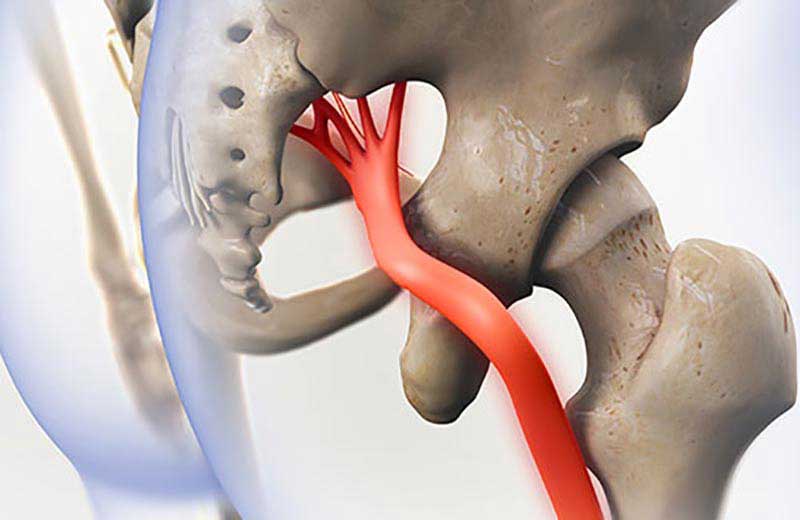

درمان عصب سیاتیک پای چپ

درمان عصب سیاتیک پای چپ درد سیاتیک یکی از شایعترین درمان درد عصبی در جهان است که بسیاری از افراد آن را تجربه میکنند. این درد زمانی ای...

درمان زود عصب سیاتیک پای راست

درمان زود عصب سیاتیک پای راست یکی از شایعترین دلایل کمردرد و دردهای تیرکشنده پا است که میلیونها نفر در سراسر جهان را درگیر میکند. ای...

درمان دیسک کمر بدون جراحی

درمان دیسک کمر بدون جراحی دیسک کمر ، فتق دیسک یا بیرون زدگی دیسک یکی از شایعترین علل دردهای ناحیه کمر و پا است که میلیونها نفر در سرا...